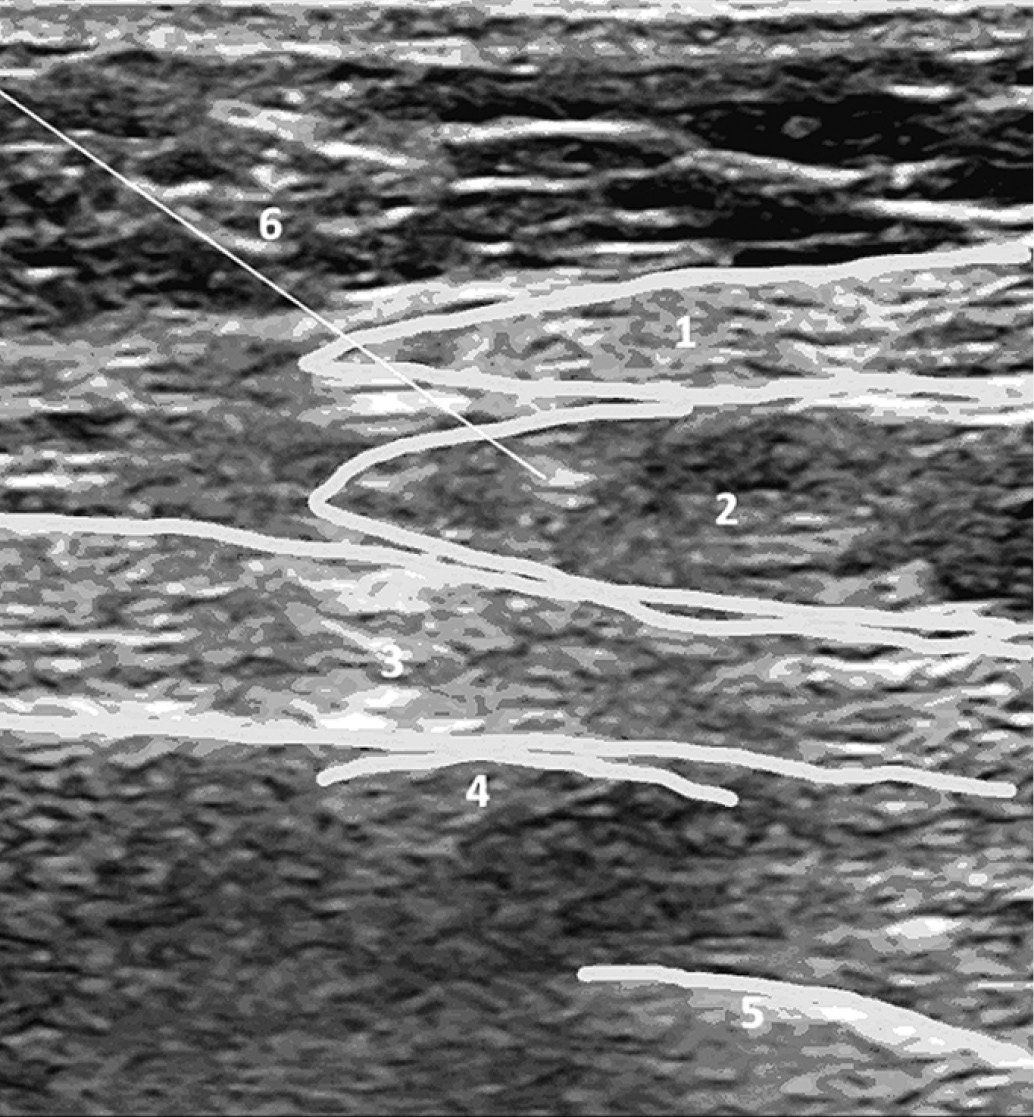

Во время процедуры пациент лежит на спине с отведённой рукой. Датчик помещается поперёк подмышечной впадины, где широчайшая мышца спины более заметна (рис. 2).

Рис. 3. Сонографические ориентиры выполнения блокады нервов нейрофасциального пространства передней зубчатой мышцы

Fig. 3. Sonographic guidelines for the implementation of the SAPB

Примечание: во время процедуры визуализируются широчайшая мышца спины − 1, передняя зубчатая мышца − 3, V ребро − 4 и плевра − 5. После определения сонографических ориентиров через иглу 22G – 6 вводится раствор местного анестетика – 2. Рисунок авторов.

During the procedure, the latissimus dorsi muscle is visualized – 1, serratus anterior muscle – 3, V rib – 4 and pleura – 5. After determining sonographic landmarks, a local anesthetic solution – 2 is injected through a 22G – 6 needle. Authors’ drawing.